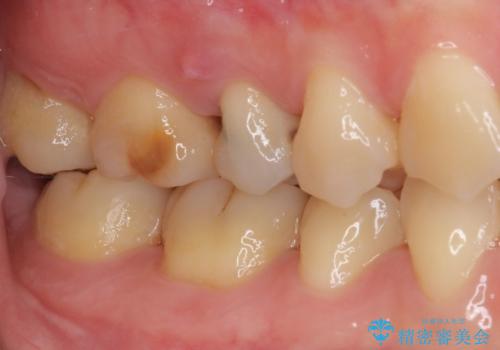

- 近医にて右上奥歯に大きなむし歯があると指摘されたとのことで来院された患者様です。

診査の結果、既に歯の神経は失活して変色しておりましたが、特に痛みは認めませんでした。

根管治療を行った後にオールセラミッククラウンにて補綴することとしました。